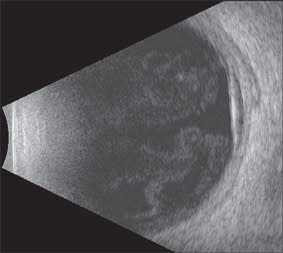

Figure 5. OCT of the left eye, highlighting subretinal fluid and macular edema.